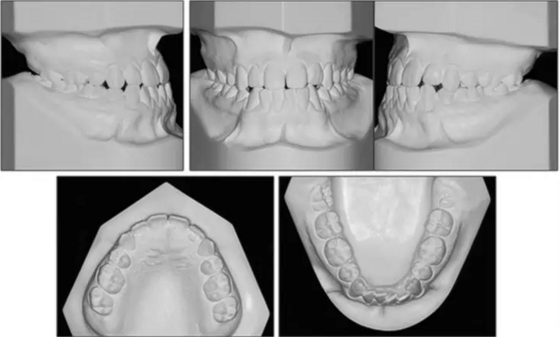

口內(nèi)相示:尖牙、磨牙完全III類關(guān)系,覆蓋2mm,覆合端端關(guān)系,上頜中線左偏2mm,下頜牙列擁擠5mm。

口內(nèi)相及模型:雙側(cè)磨牙、尖牙I類關(guān)系,良好的牙尖交錯關(guān)系,覆合、覆蓋正常。